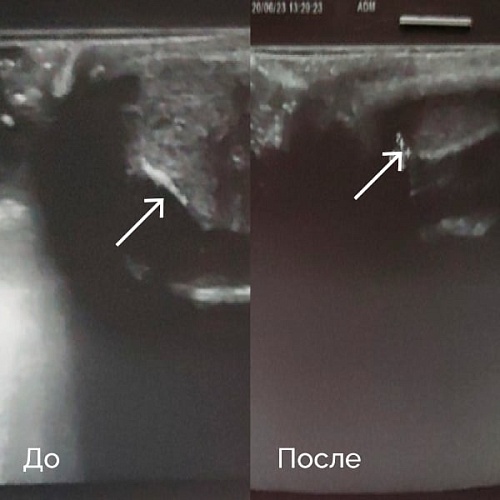

Для иллюстрации приводим клинические наблюдения результатов лечения болезни Пейрони.

Пациент П., 45 лет

Обратился с жалобами на искривление полового члена в течение 1 года. По данным УЗИ определяется гиперэхогенное образование (бляшка) размерами до 10 мм. Проведен курс УВТ в количестве 8 процедур. Через 5 сеансов пациент отметил значительное улучшение — уменьшение искривления полового члена. После курса лечения по данным УЗИ полового члена по дорсальной поверхности в белочной оболочке лоцировано несколько гиперэхогенных точечных и линейных аваскулярных фрагментированных включений размерами от 1,1 мм до 2,0 мм (рис. 1).